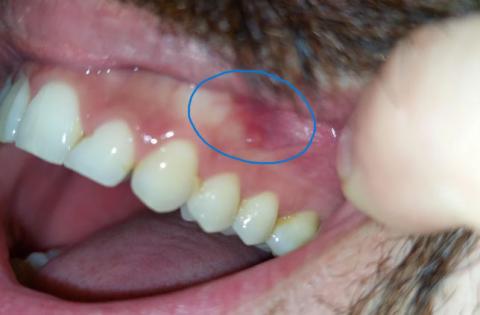

What Is Seen in This Case

The image shows a localized red area on the gum near the side teeth, highlighted in the photo. The teeth themselves appear mostly intact, but the gum tissue in this area looks inflamed and irritated. This type of lesion is often related to local trauma, irritation, or early infection.

This condition should be monitored closely, even if pain is mild.